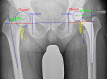

Methods: In this prospective study a consecutive series of 125 patients were randomized to either navigation-guided or fluoroscopy-controlled THA using sealed, opaque envelopes. All patients received the same cementless prosthetic components through an anterolateral MIS approach while they were in a lateral decubitus position. Leg length, global or total offset (representing the combination of femoral and acetabular offset), and femoral offset differences were restored using either navigation or fluoroscopy. Postoperatively, residual leg length and global and femoral offset discrepancies were analyzed on magnification-corrected radiographs of the pelvis by an independent and blinded examiner using digital planning software. Accuracy was defined as the relative postoperative difference between the surgically treated and the unaffected contralateral side for leg length and offset, respectively; precision was defined as the absolute postoperative deviation of leg length and global and femoral offset regardless of lengthening or shortening of leg length and offset throughout the THA. All analyses were performed per intention-to-treat.

Results: Analyzing the relative accuracy of leg length restoration we found a mean difference of 0.2 mm (95% CI, -1.0 to +1.4 mm; p = 0.729) between fluoroscopy and navigation, 0.2 mm (95 % CI, -0.9 to +1.3 mm; p = 0.740) for global offset and 1.7 mm (95 % CI, +0.4 to +2.9 mm; p = 0.008) for femoral offset. For the absolute precision of leg length and global and femoral offset equalization, there was a mean difference of 1.7 ± 0.3 mm (p < 0.001) between fluoroscopy and navigation. The biomechanical reconstruction with a residual leg length and global and femoral offset discrepancy less than 5 mm and less than 8 mm, respectively, succeeded in 93% and 98%, respectively, in the navigation group and in 54% and 95%, respectively, in the fluoroscopy group.